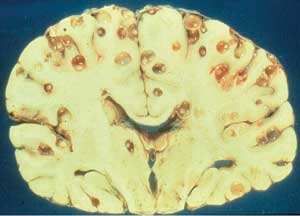

A perennial favorite! Worms, cysts and brains! What an awesome lifecycle! [&o]ORIGINAL: Cap Mandrake

ETA: If this doesn't make your scalp itch, nothing will.

- cysticercus.jpg (9.09 KiB) Viewed 138 times

Most of the time, as I understand it, yes. Provided there aren't too many cysts in particularly important areas of the brain. It depends on the severity of infection. The picture I've included above was obviously collected from a postmortem examination.

Believe it or not what you saw above was relatively mild. I've seen brains ( post-mortem ) with holes the size of golf balls throughout. Once treated an Eastern European man who had undiagnosed cerebral TB which essentially ate away his entire frontal lobe - where your executive functioning and personality are based - and, over the course of 4 days, turned from an adult 30some year old male into the equivalent of a 3 or 4 year old with no power of speech, no ability to toilet himself etc. The CT Brain showed the replacement of the frontal lobes with a ball of pus. Pretty horrific thing to see. Even worse when I had to break it to his wife and kid. Wife had no english, it was an emergency so I had to use the 10 year old kid to translate for me. Pretty sure he'll be traumatised for life "Tell your mother your father's brain has been eaten and he WILL die. " *sigh*

Basically if you can actually see a lesion on the brain with the naked eye in a post-mortem shot like that then you can be pretty sure it wasn't a mild injury. It isn't a perfect rule of thumb but it is pretty good.

Also, if you are looking to determine whether or not something will impact intellect then look at the outer portion of the brain, the 0.5cm closest to the surface. That's where "grey matter" lies. If you find damage there then you are losing stuff which is very hard to replace as that stuff is what "thinks" and decides on actions and movements. As you go deeper you get into white matter which is, essentially, lots of pipelines carrying the data from the grey matter to the spine where it can get transmitted. If you've got damage in the white matter and you can reroute the signals ( not easy but possible ) then you've got no loss of function. If they grey matter is FUBAR then plasticity comes into play but, really, I wouldn't be hopeful.

Also, i don't think Cysticercus worms actually "eat" the brain: they are walled off in encapsulated cysts and grow slowly absorbing nutrients from the blood, iirc.